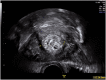

Ultrasound assessment of the postpartum uterus has a significant role to play in the evaluation of a large proportion of symptomatic puerperal women. Often the imaging modality of choice for excluding retained placental tissue, correct application of postpartum ultrasound could enable more accurate identification of women requiring surgical intervention, with consequent reduction in patient morbidity and clinical workload. This article aims to review the current understanding and application of ultrasound in the puerperium and evaluate the current evidence investigating the physiological and pathological findings of the postpartum uterus and its contents.